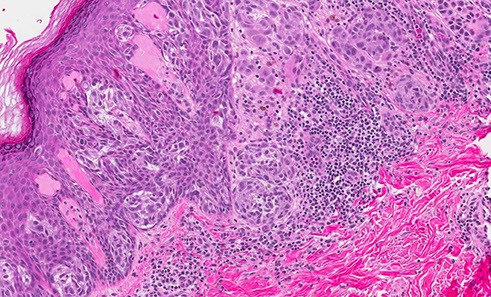

Basal cell carcinoma (BCC)

NON-lethal skin cancer; locally invasive but almost never mets

- MC of ALL cancers

- MC in skin exposed areas of body

~ 90% bwt hairline and upper lip

~ 5% recurrence

- can look like dermatitis clinically or actinic keratosis

Rolled edges w central ulceration

- pearly papules w telangiectasias; palisading nuclei

~ form thymidine dimers due to sun exposure

3 criteria for dx: palisading, clefting and nesting

- myxoid change around edge of tumor, that can cause clefting artifact

- "Basal cells stroma" - changes with dilated vessels, lymphocytes and mucin around BCC

- irritated BCCs can get squamoid differentiation, probably do not need to mention unless is very diffuse

- infiltrating / sclerosing / morpheaform (all the same) may be more locally aggressive form of BCC, that may need to be more aggressively treated, can have perineural invasion if infiltrates really deep, and have higher rates of recurrence

- fibroepithelioma of Pinkus is probably just a form of BCC and should be treated as such

- can have areas of pleomorphism in BCC, if it merges into more normal looking BCC, probably do not need to worry or treat differently

- BCC can also blend into a part of the tumor that has large zones with fluffy granular cells that is called "granular cell variant of BCC" which usually transitions into areas of more normal looking BCC - can look like melanoma

- also can have clear ceell variant of BCC that should also transition into more normal looking BCC

- amyloid in BCC is probably just a breakdown product of degenerative keratin and does not mean that the pt has systemic amyloidosis (can be seen in other adnexal tumors

- may have stromal retraction around tumor

BCC can be pigmented and look like melanoma clinically

IHC: (+) CD34 (may be negative), BCL-2 (strong and diffuse)

- negative CK20+ Merkel cells (negative at least in tumor islands)

Tx: Moh's micrographic surgery

- if BCC is superficial pattern, dermatologist may choose to treat with topical agents

Nodular BCC with nesting, clefting and pallisading

Squamous differentiation in BCC

Superficial pattern BCC

Morpheaform / sclerosing / infiltrative BCC

Subtle, invasive BCC

Infiltrative BCC

Pigmented BCC

Adenoid BCC

Fibroepithelioma of Pinkus - just another for of BCC, should treat as such

Atypia in BCC- no need to worry

Granular cell variant of BCC

Clear cell variant of BCC

Amyloid in BCC - an normal finding, the pt has not systemic amyloidosis